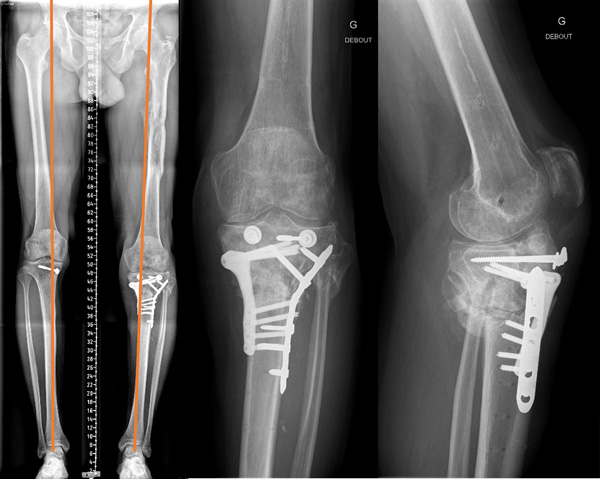

Pre-operative planning

Aimed for slight varus (symetric)